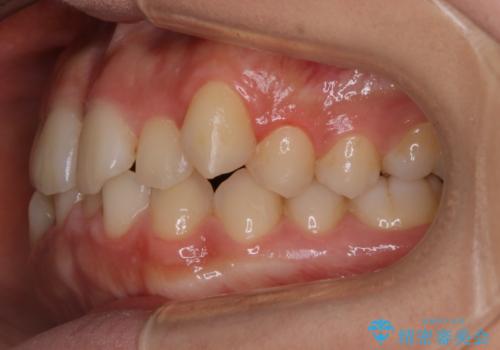

【非抜歯】すきっ歯と噛み合わせの治療

- 上の前歯のすきっ歯と下の前歯のガタつきを主訴にご来院されました。

噛み合わせの改善も同時に進めつつ、主訴の部分も効率的に治していくためマウスピース装置でゴムかけを行いながら治療を進めていきました。

正中離開(すきっ歯)

真ん中の歯が左右に開いてしまい隙間ができてしまう状態を「正中離開」といい、俗にすきっ歯と呼ばれています。

隙間を埋めていく方向に歯を移動させることで改善していくケースが多く、比較的治りやすい不正咬合のひとつとされています。

しかしながら、歯が捻じれていたり、噛み合う歯との位置関係によっては治療が難しくなる場合があります。